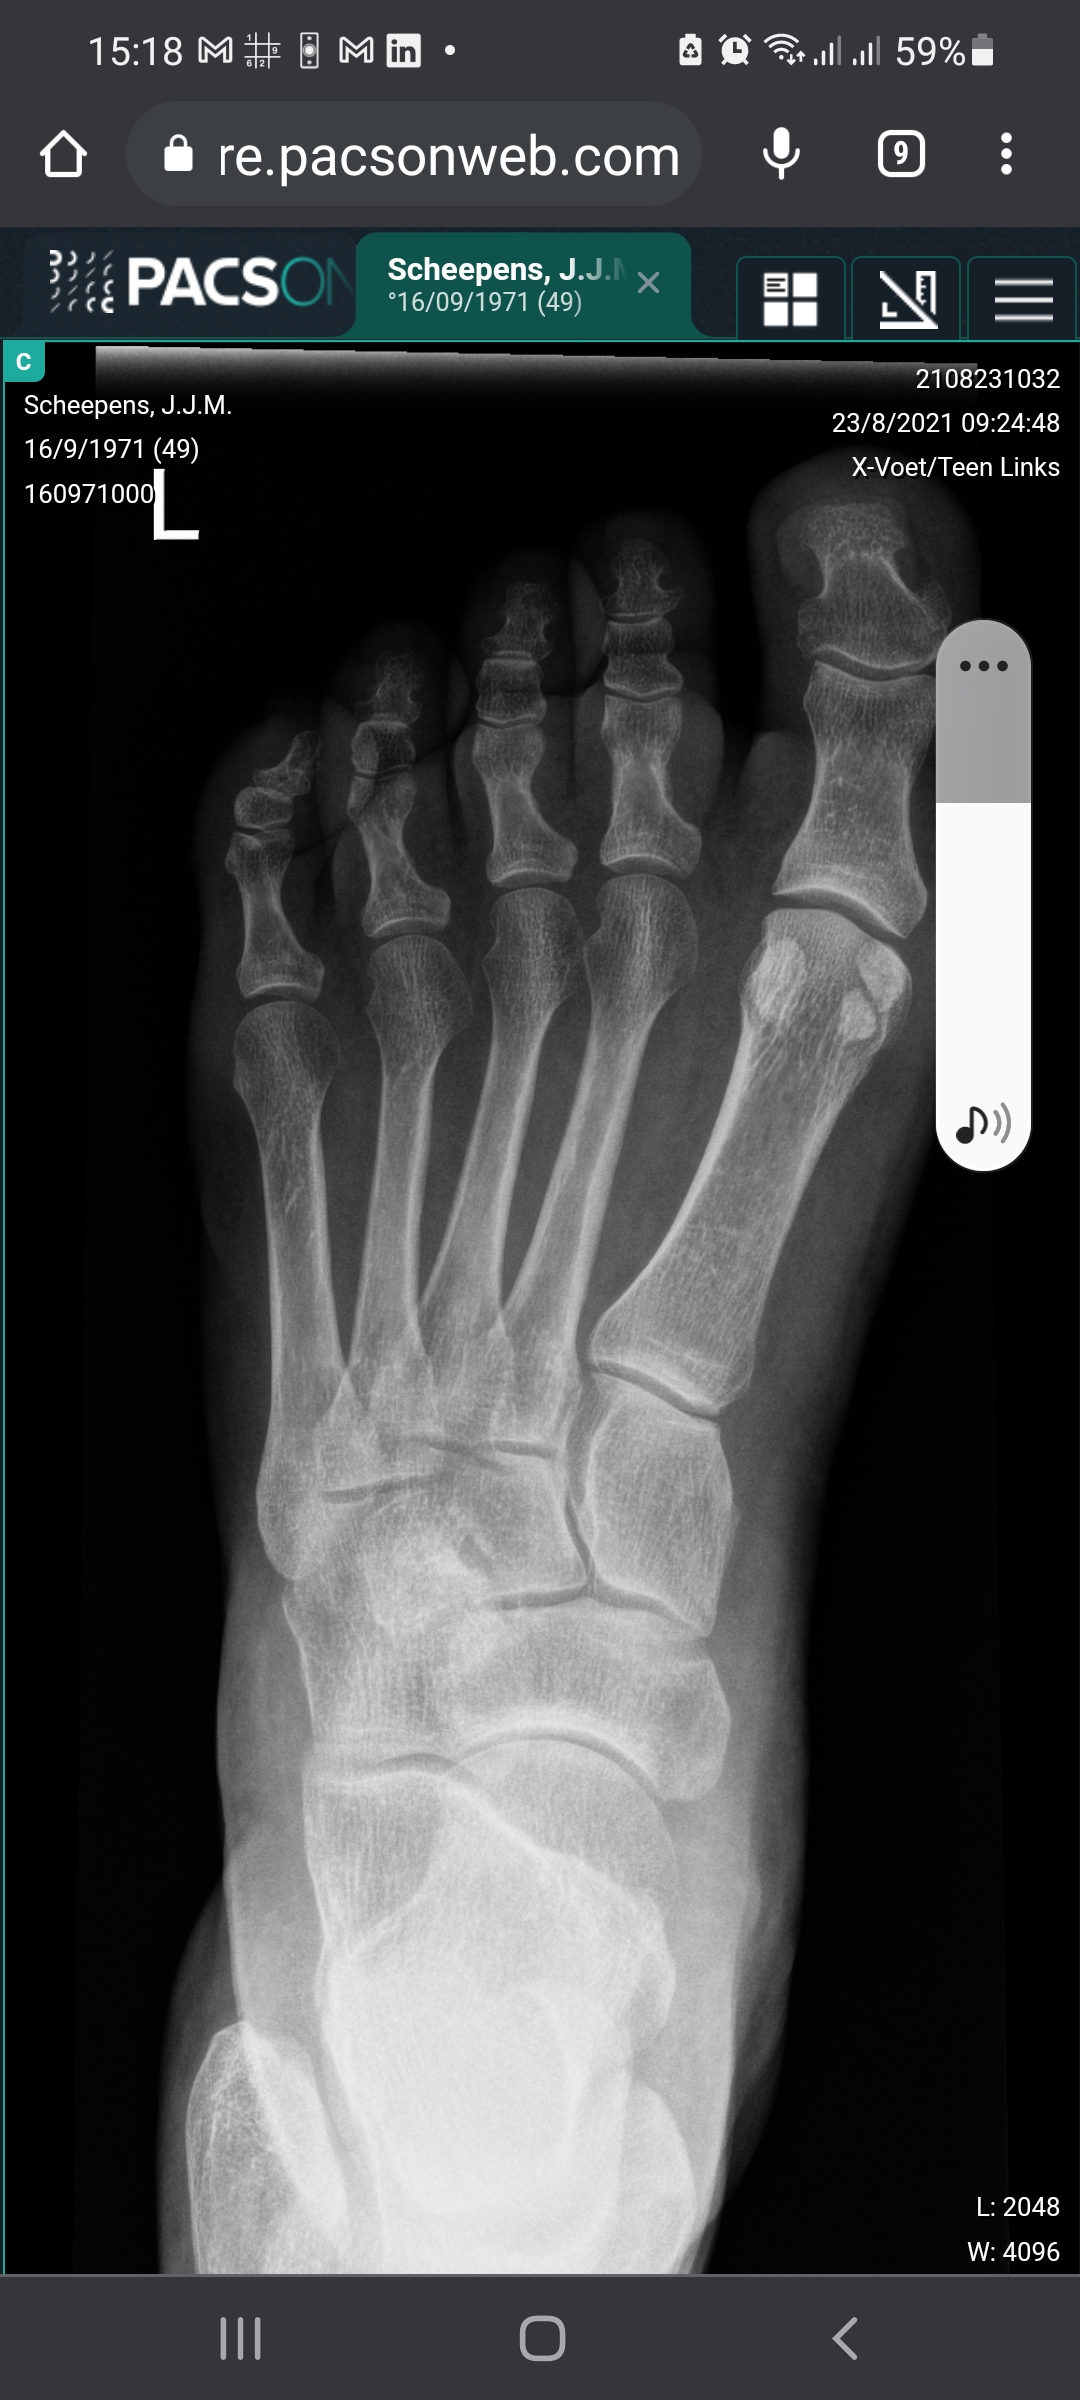

Vanmorgen in allerijl naar de huisarts. Hopen tegen beter weten in dat ik niet naar het ziekenhuis hoefde.

En ik FEACH®: want wat een lieve vrienden heb ik zeg! Nooit gedacht dat ik zo blij en dankbaar zou zijn om een gipskamer binnen te komen. Leve de 'Kiss & Ride' bij het ziekenhuis.

En nu? Hopen dat ik gauw weer mijn hakschoenen aan kan. Leve de spalk! Of ik stevige schoenen had. Na diep graven in mijn geheugen kon ik maar één ding bedenken.

#feach #sextortionboek #vrienden #positivevibes #hoekschewaard #botbreuk #rust #jebentnietalleen #anwb